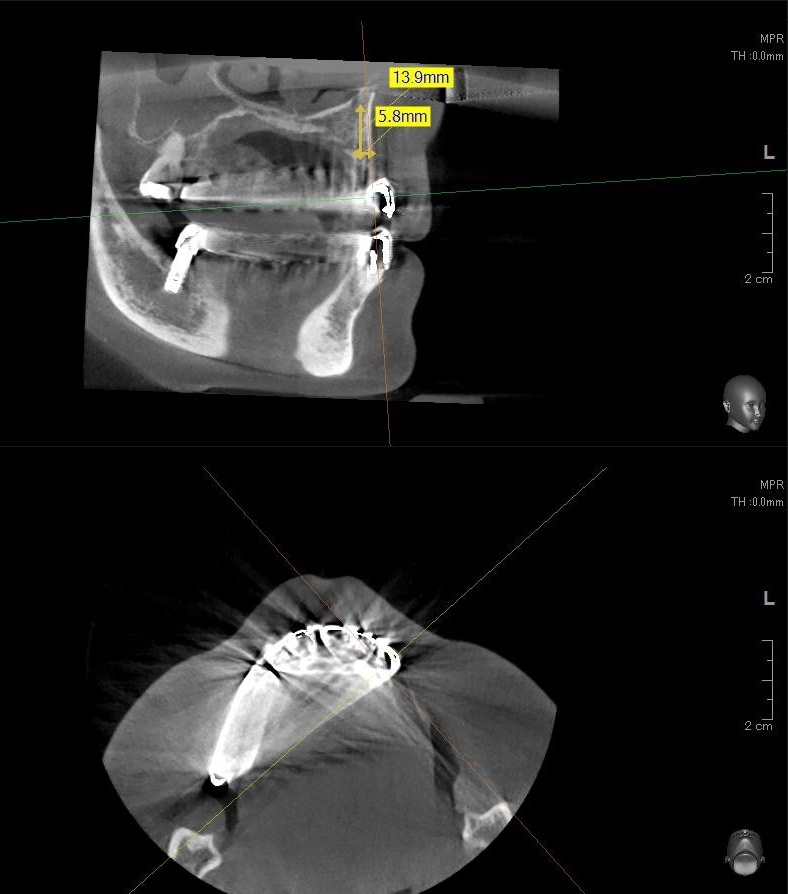

今回の患者様はインプラント植立を希望され、左上3番目の植立が決まりました。

ドリルの先端を細い物から徐々に大きい物に変えながら、植立するインプラント体のネジの部分を除いた胴の部分の太さに合わせた大きさの穴を開けていきます。

開けた穴に、専用道具を使ってネジを締めるように長さ2センチ程のインプラントを骨に埋め込んでいきます。

しっかりとインプラント埋め込まれた後は、動揺がないか、噛んだ時に当たらないかなどを確認して、最後にパノラマ写真を撮影して今回のオペは終了となりました。